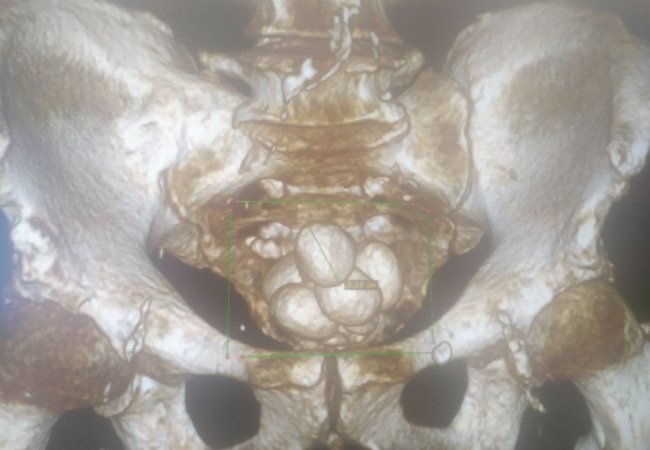

74-річного чоловіка госпіталізували у важкому стані. Лікарі діагностували низку хвороб, частина з яких у запущених стадіях: доброякісна гіперплазія передміхурової залози, хронічна затримка сечі, множинні камені сечового міхура, двобічний уретерогідронефроз, гостра ниркова недостатність.

Першим етапом виконано цистолітотомію з епіцистостомією. Пацієнту забезпечили відтік сечі через спеціальну трубку, адже природній спосіб уже був неможливий. Далі лікарі приступили до видалення каменів великих розмірів, якими був наповнений сечовий міхур пацієнта (аж 12). Лапароскопічний спосіб у даному випадку був неможливим. Тож лікарі провели відкриту операцію.